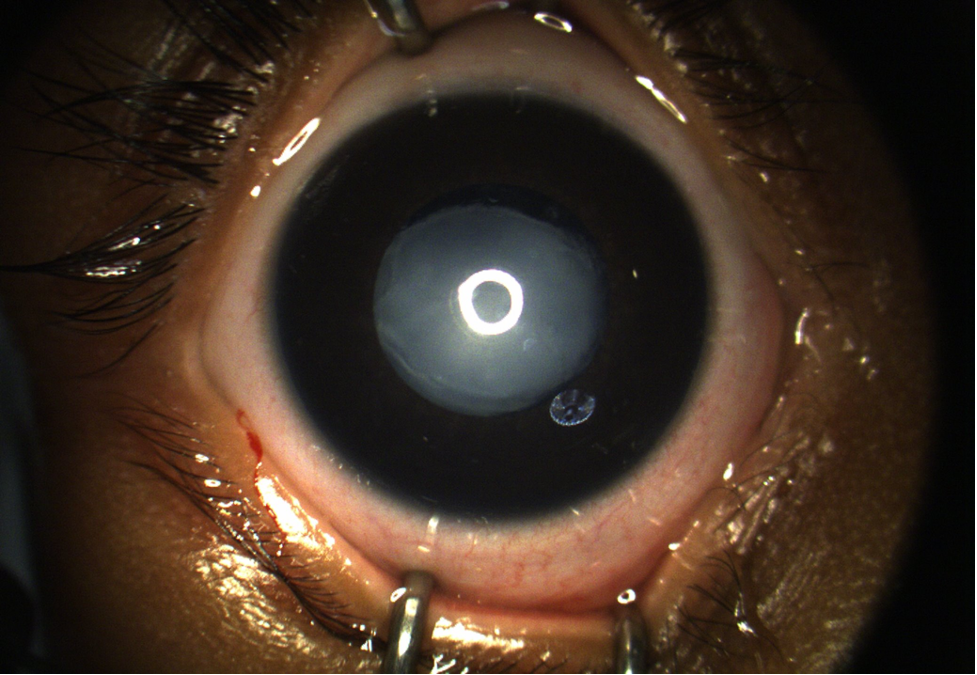

Penetrating Ocular Fishhook Injury

Specialty: Corneal and External Diseases

Include in Catalogue?: No

Presenter(s): Humberto Salazar, III, MD

Faculty Discussant(s): Harry W. Flynn, Jr., MD; Nicolas A. Yannuzzi, MD

Discussant(s): Diana M. Laura, MD

Penetrating Ocular Fishhook Injury A patient with a history of stroke, hypertension, and pseudophakia of both eyes, presented with eye trauma while fishing without protective eyewear. While reeling in, his fishhook flew out of the water and hit him in the right eye. On presentation, his right eye v…

Type: Online Grand Rounds

Include in Catalogue?: Yes

Presenter/Faculty: Flynn, Laura, Salazar, Yannuzzi